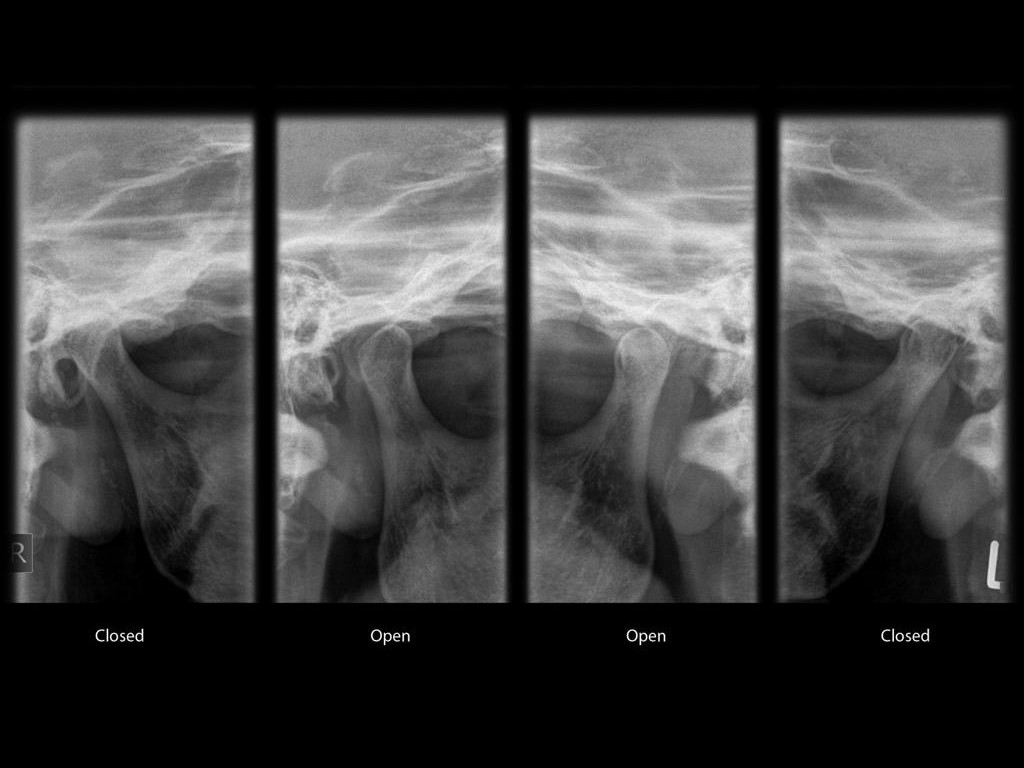

| Zdjęcie stawów skroniowo-żuchwowych | 200 |